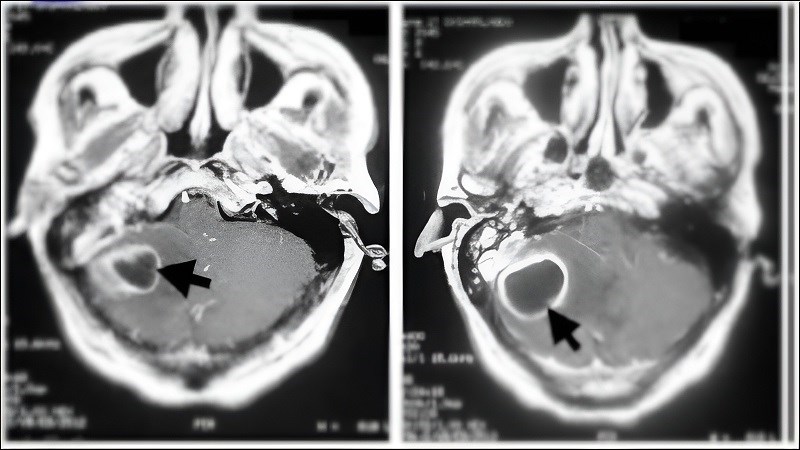

- Biến chứng nội sọ xảy ra ở 7 đến 23% trường hợp mắc bệnh: Viêm não (0,9%) và màng não (0,3%), áp xe tiểu não, áp xe thùy thái dương, áp xe dưới màng cứng (6,9%) hoặc ngoài màng cứng, huyết khối xoang tĩnh mạch bên (5,3%).

Áp xe tiểu não là một trong các biến chứng của viêm tai xương chũm